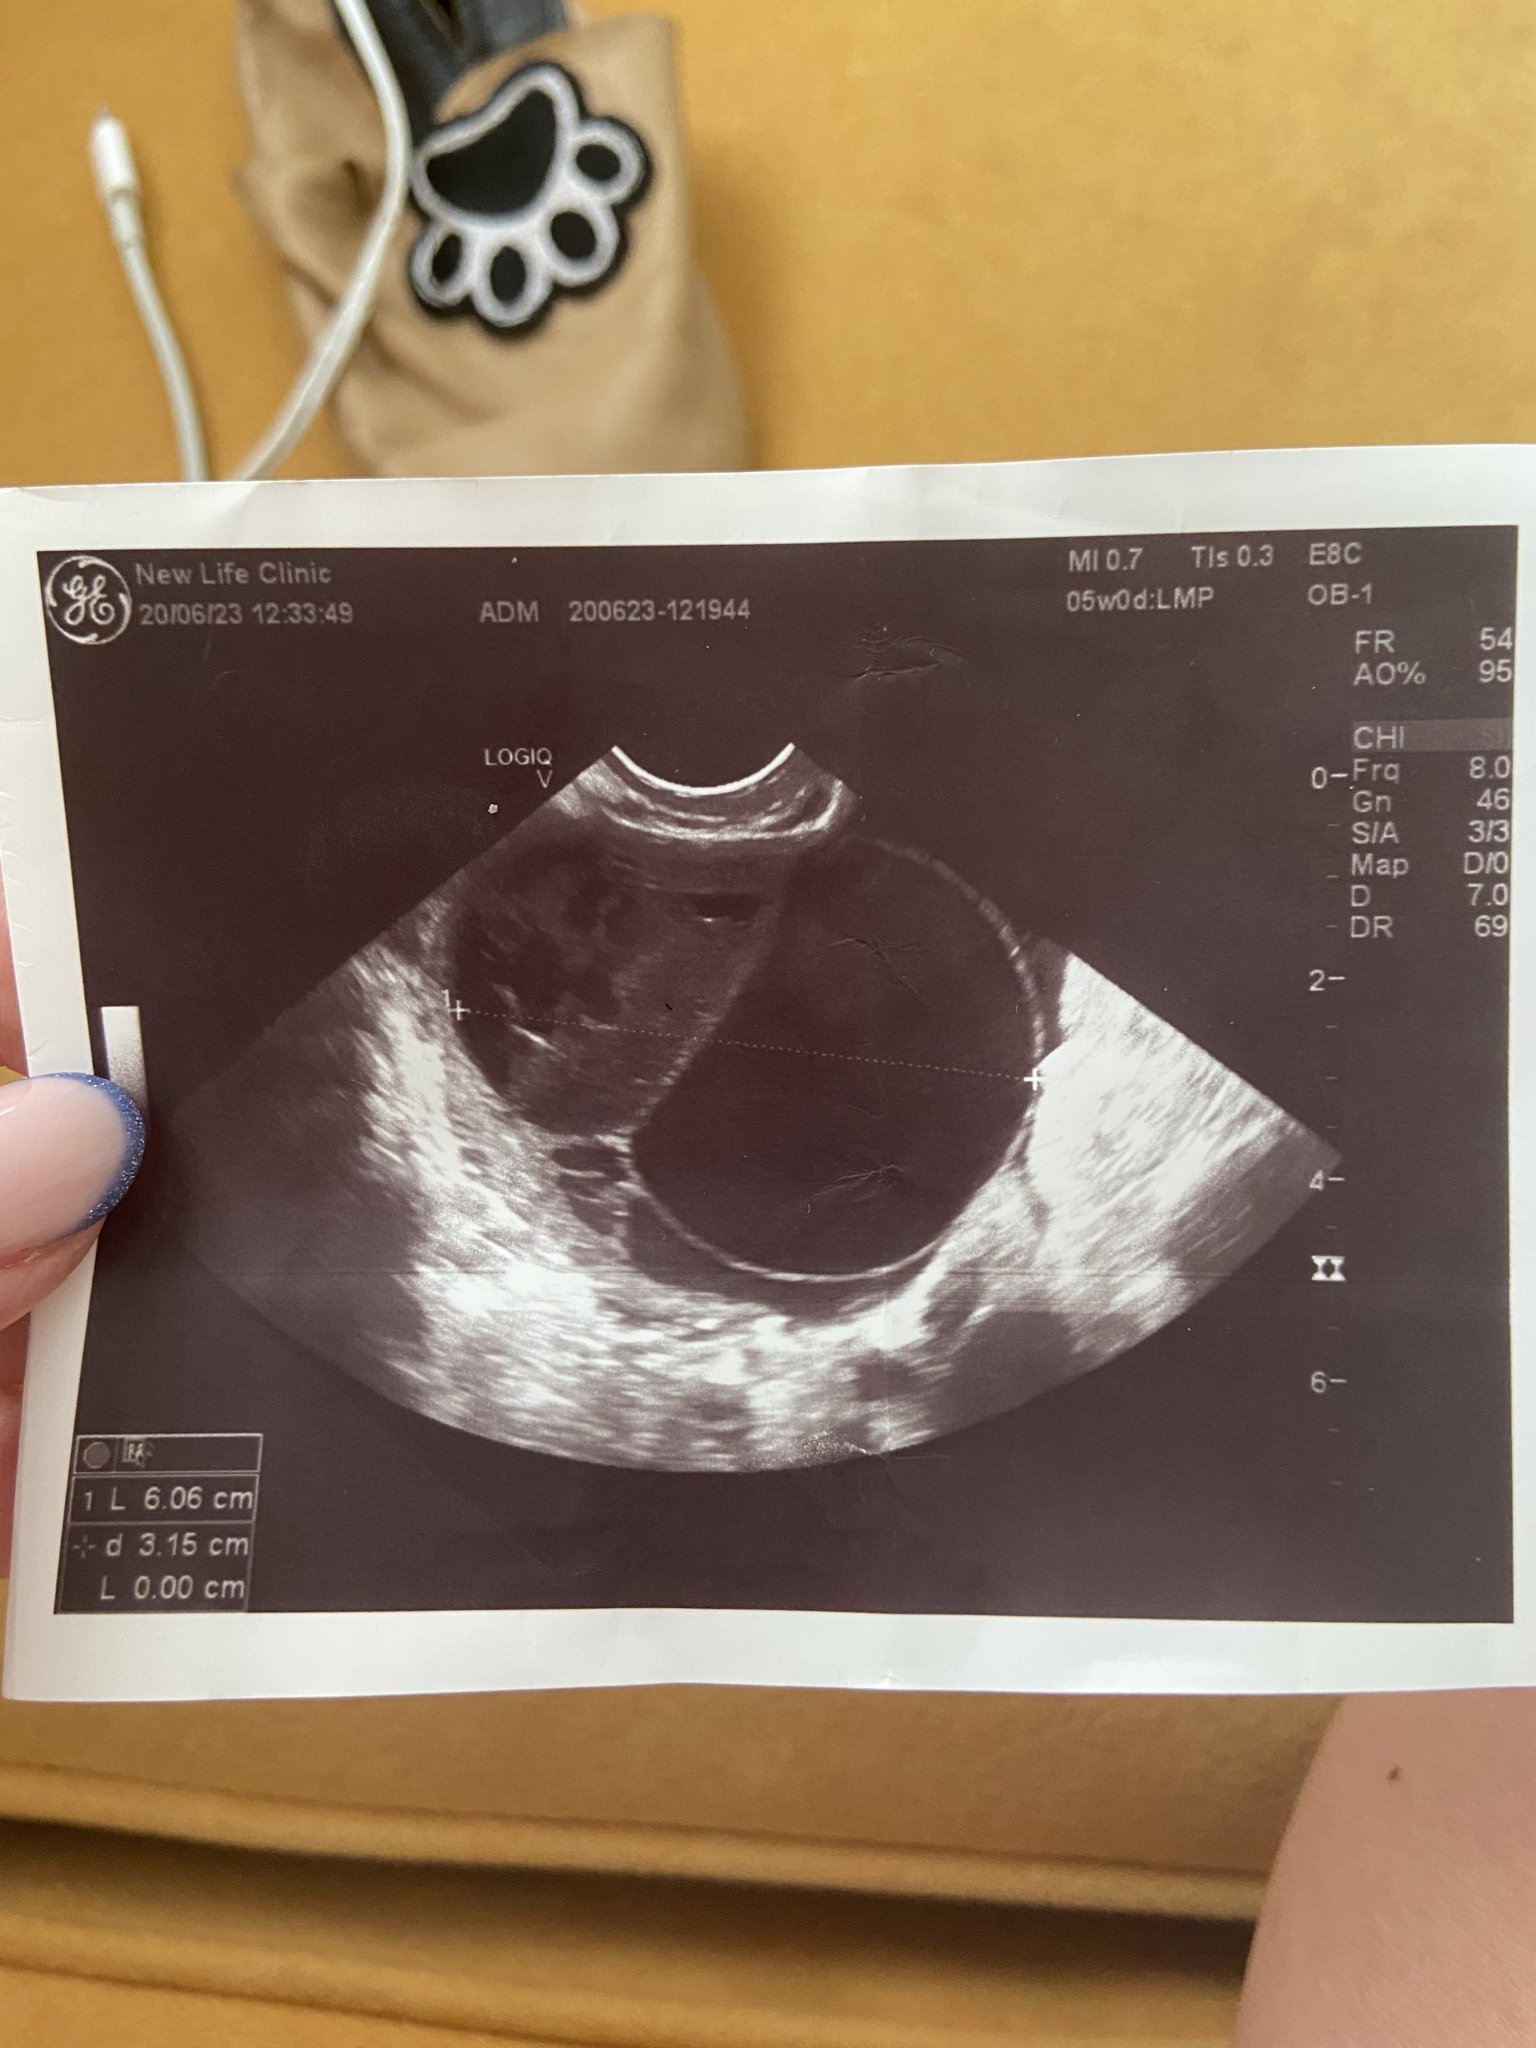

Ами да, и аз никъде никаква информация не намирам в нета, но ето че явно става. Имам яйчника на снимка от ехографа. В момента е нараснал до 6 см. Пак казвам, не съм приемала никакви лекарства свързани с проблемно забременяване никога. Като изключим едни хапчета за хрема турски, дори не знаех, че существуват, но докато бяхме на почивка там се разболях и ми дадоха в аптеката. Това е единственото лекарство, което съм приемала последните 2-3 месеца.

Ще прикача снимка. Вижда се много добре. Но ще потърся и друг лекар следващата седмица.